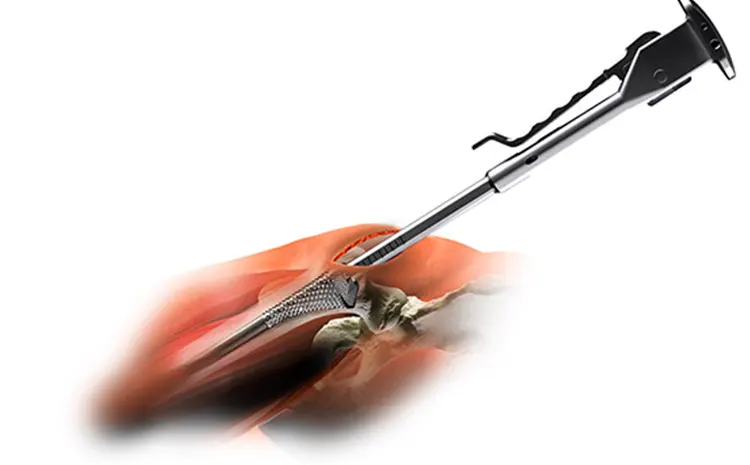

Η SuperPath έχει χαρακτηριστεί ως micro προσπέλαση, καθώς η τομή στο δέρμα είναι συνήθως 6-8 εκατοστά. Το σημαντικότερο πλεονέκτημα είναι ότι δεν τέμνεται κανένας τένοντας που περιβάλλει την άρθρωση του ισχίου, γεγονός που επιτρέπει την ταχύτερη κινητοποίηση και αποκατάσταση του ασθενούς.

- Με χρήση ειδικών αγκίστρων και εργαλείων ολοκληρώνεται η προετοιμασία του μηριαίου οστού και της κοτύλης ώστε να τοποθετηθούν οι τελικές προθέσεις.